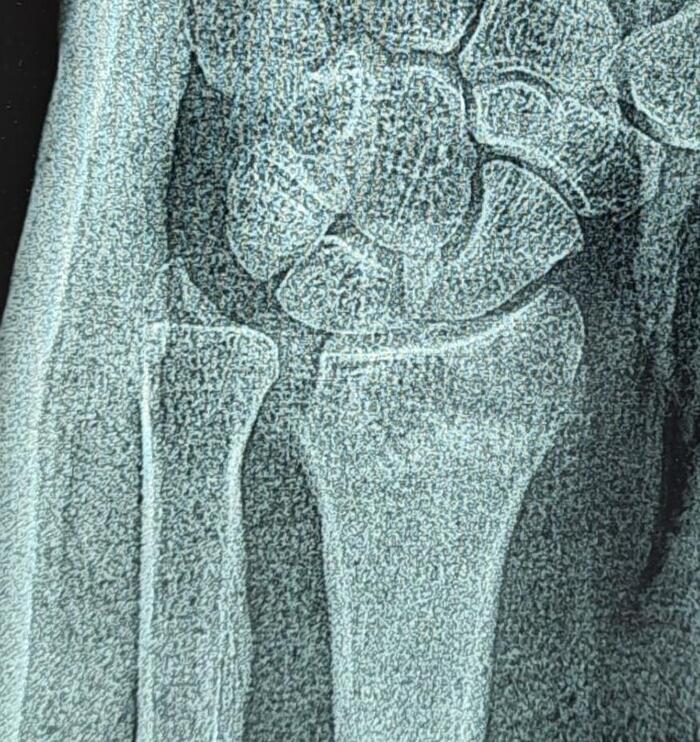

На рентгенограмме костей таза: суставные щели тазобедренных суставов неравномерно сужены, с выраженными краевыми остеофитами в верхне-наружном отделе. Субхондральный склероз суставных поверхностей. Головки бедренных костей уплощены, скошены, структура костной ткани с участками просветления чередующихся с участками остеосклероза. Шейки бедренных костей расширены. Заключение: Двусторонний коксартроз 3 ст. Асептический некроз головок бедренных костей.